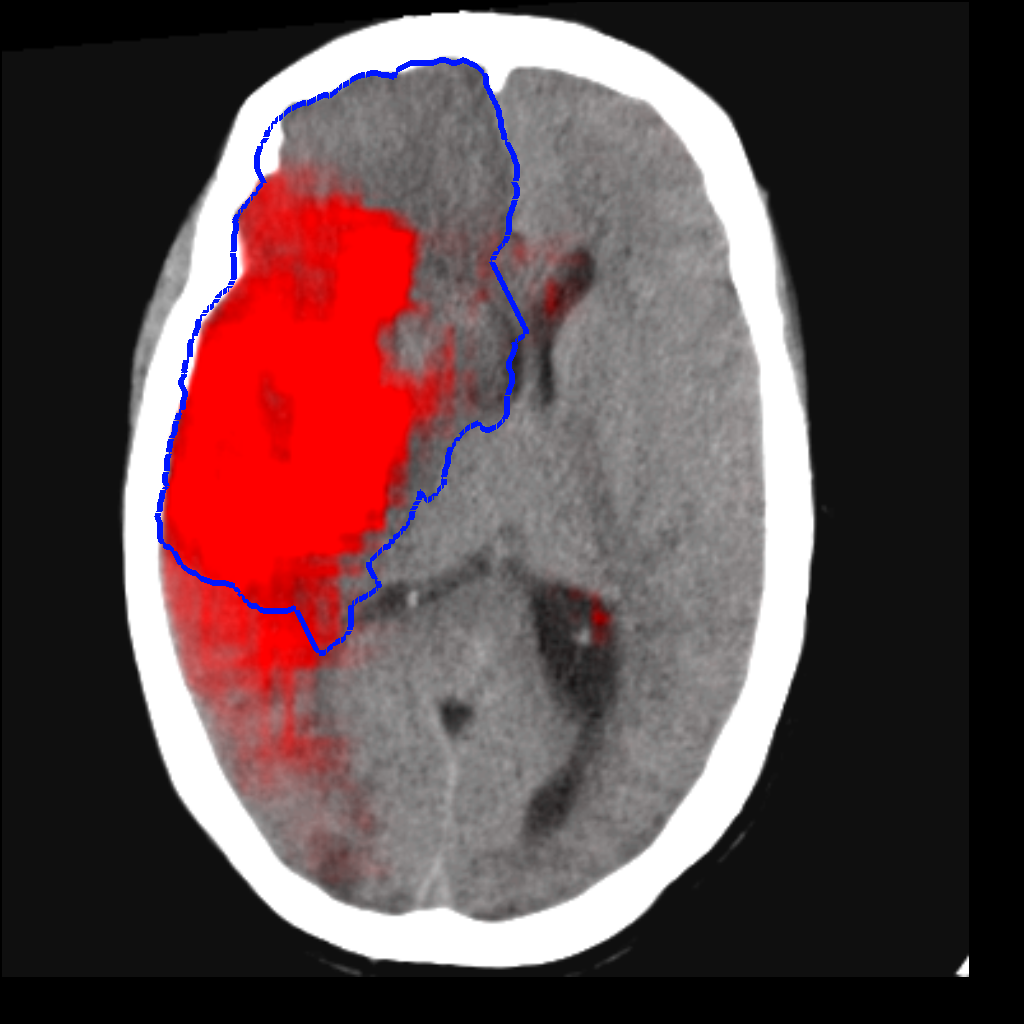

Fig. 3 shows a scatter plot and a Bland-Altman plot of the true and predicted volumes for all subjects in the testing folds using the proposed method. The mean volume error is -2.8 ml (the prediction is a slight underestimation) and the mean absolute volume error is 36.7 ml. The mean Dice score is 0.48. A representative set of predictions is shown in Fig. 4.